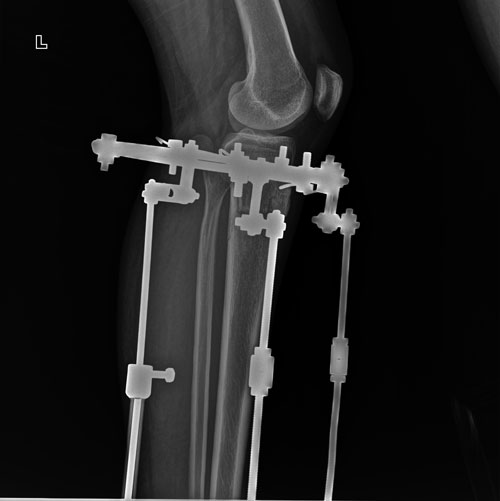

Дата операции 01.06.2018г.

Дата снятия аппаратов 29.08.2018г.

Срок сращения 88 дней.